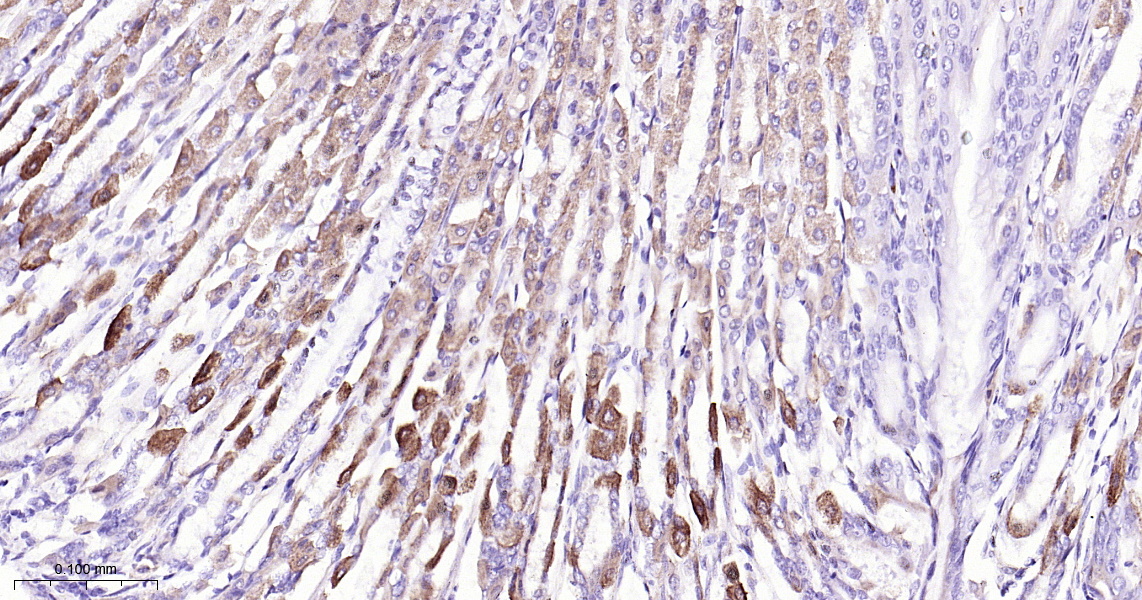

• IHC-P

IHC-P IHC-P1:50-200